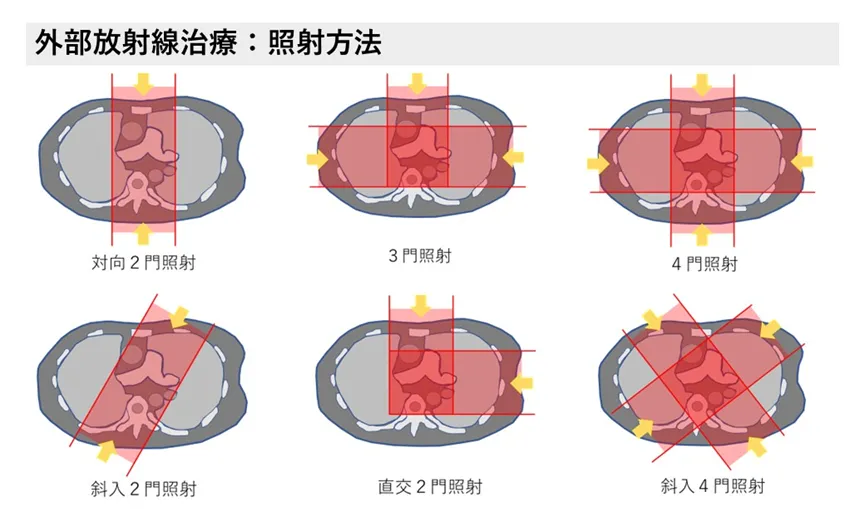

传统放疗(X射线)的能量是沿其穿透路径释放的。射线穿过的所有正常组织都会累积辐射剂量,因此造成的损伤是一种“贯穿路径上的叠加损伤”。